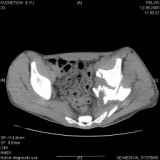

Уважаемые коллеги! Хотелось бы услышать совет по тактике лечения представлленого больного.Поступил после лечения в одном изотделений области. Травма 2,5 месяца назад. После выведенияиз шока был произведен остеосинтез перелома бедра, предплечья, до перевода к нам проводилосьвытяжение по оси шейки бедра за стержень, введенный в большой вертел. На сегодня деформацияригидна, клинически мобильности не определяется. Заранее признателен. P.S. Данный вид травм не включен в перечень "высокотехнологичных операций", направить длялечения по квотам Минздрава очень сложно.

Тяжелый случай... Поздняя реконструкция такого перелома технически сложное дело, вероятность осложнений,неуд.результатов выше(на PubMed article Johnson, Mast, Matta, Letournell results of acetabular reconstruction 20-120 days after injury).

Принимая во внимание обширность реконструкции, вероятность осложнений( остеоартроз, аваскулярный некроз), которые в любом случае должны будут решаться артропластикой сустава, пожалуй, я бы не стал оперировать сейчас: складывать мозаику многооскольчатого перелома, мобилизуя фактически сросшиеяся воедино фрагменты - дело травматичное с сомнительным результатом.

Привет, Леонид. Оскольчатый высокий двухколонный перелом в такие сроки трогать не надо, т.к. это про такие переломы сказано: "кто с ножом на Ж. пойдет тот в ней и останется...".